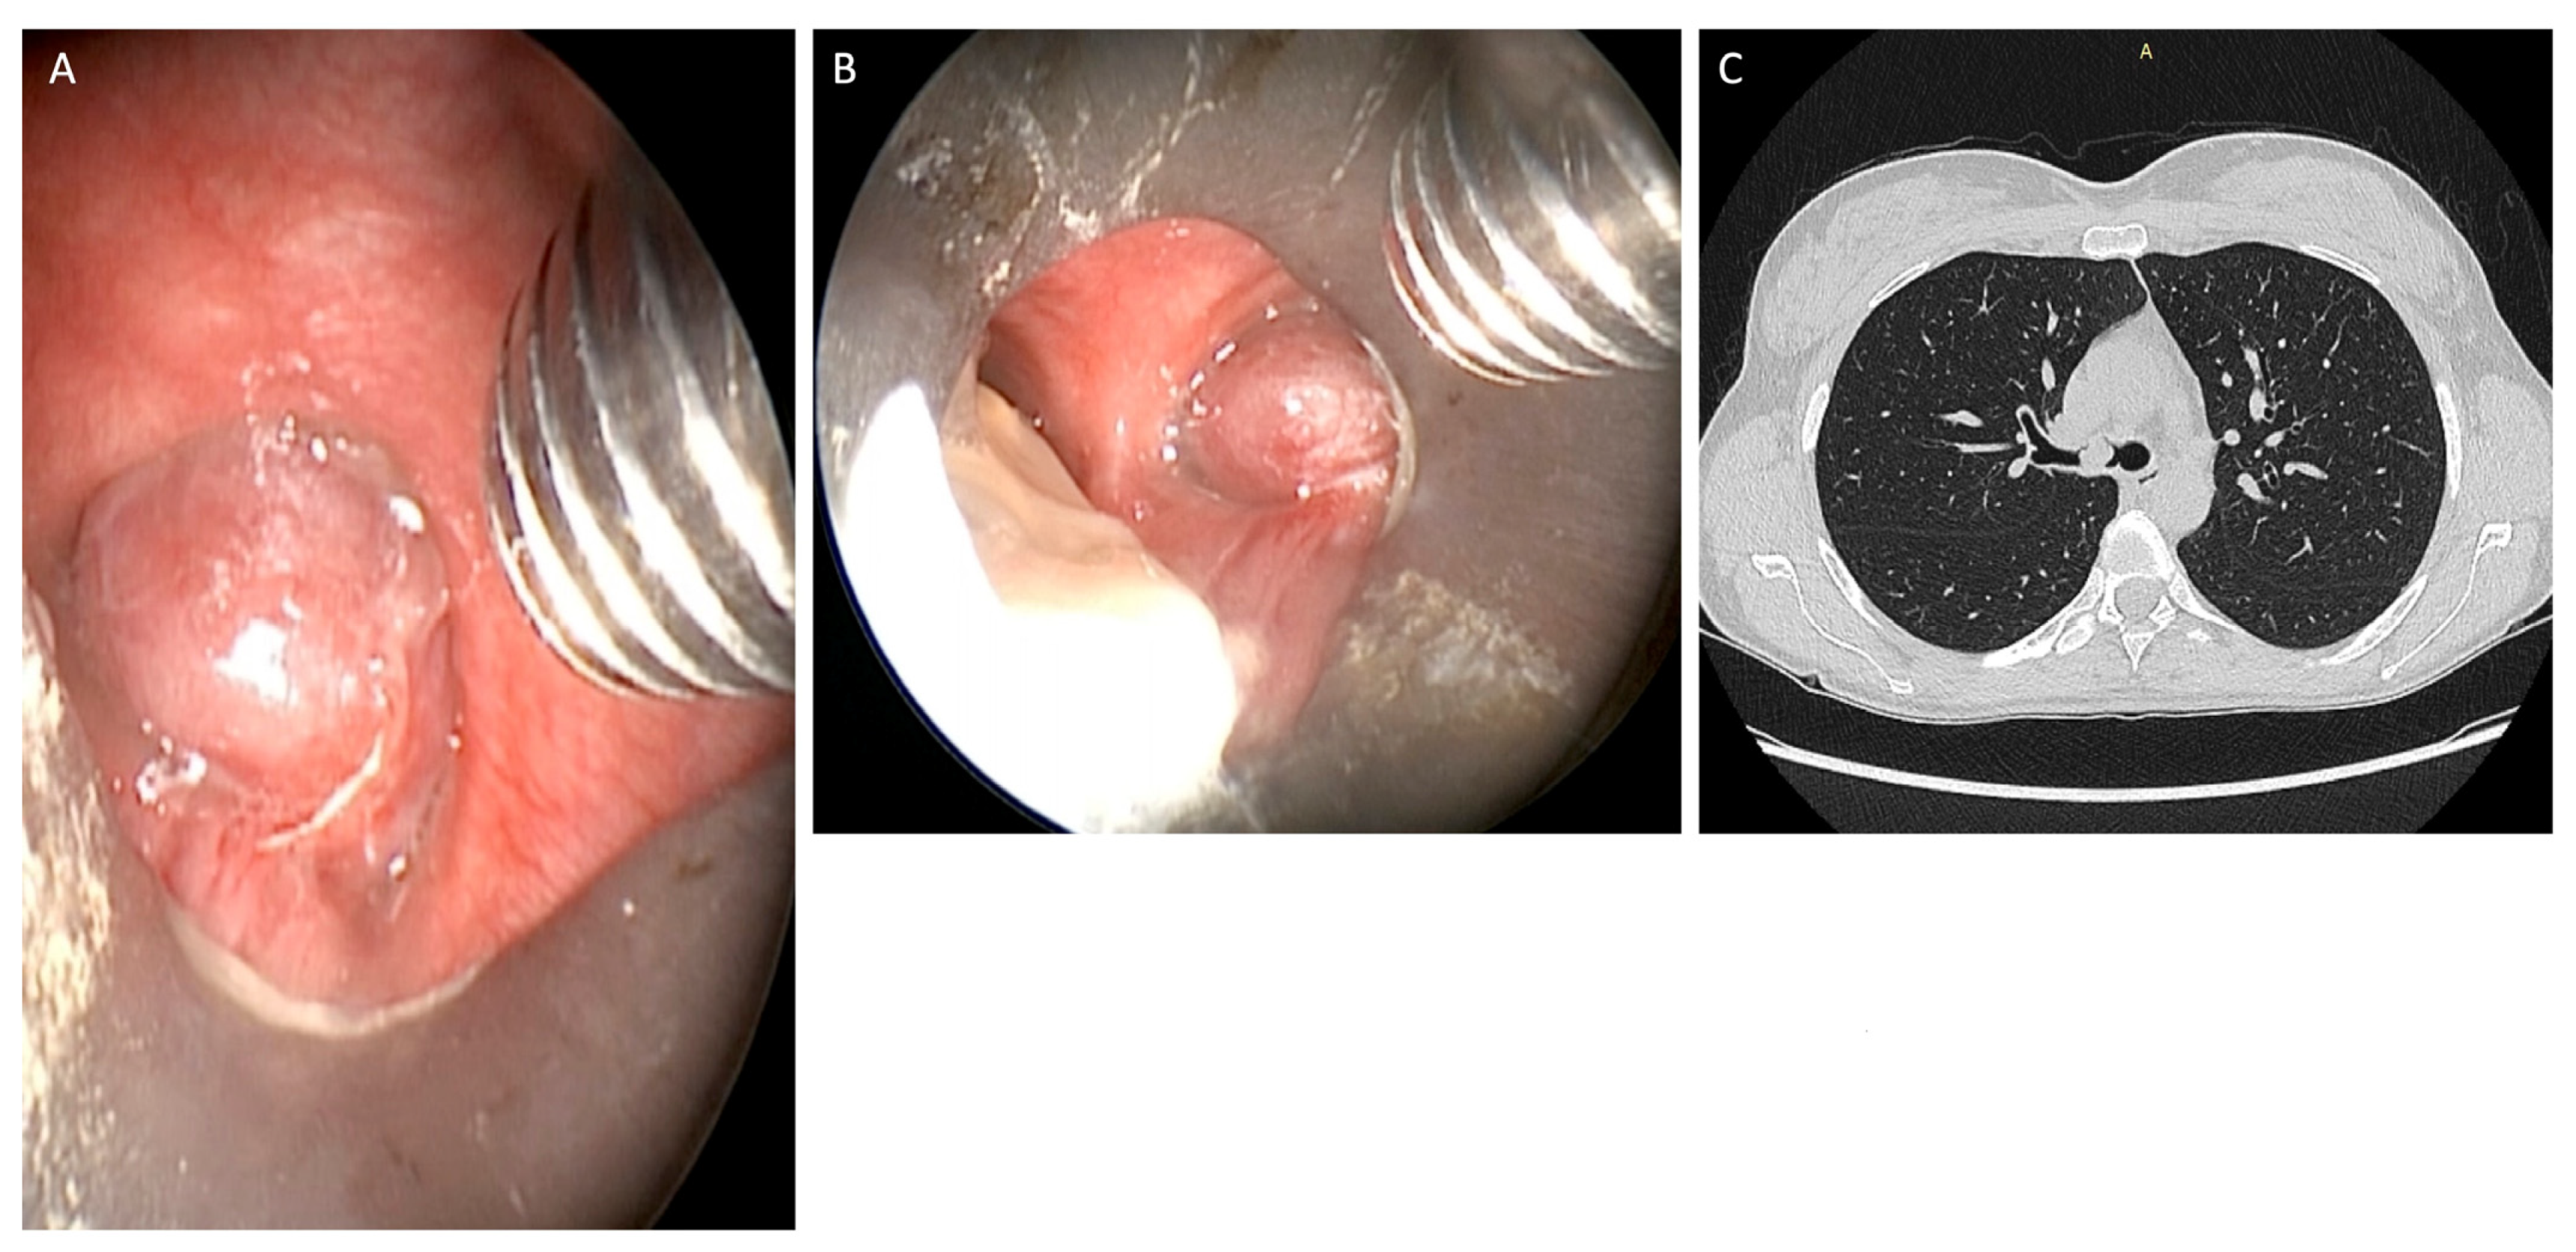

After completing the removal of the tumor in its entirety, careful control of the hemostasis was performed with an automatic peak voltage control [12] (Figure 3).

All bronchial branches were finally explored after debulking, confirming the absence of bronchial wall thickening; however, only two patients had remarkable bleeding despite the use of cautery on the cut surface of the residual tumor. We advanced the rigid bronchoscope into the right or in the left main bronchus to prevent blood flooding into the trachea, and thus accurate hemostasis was obtained by coagulation with argon plasma or Thulep Laser (Revolix, Lisa Laser Producer OMG, Katelenburg, Germany), adrenaline (1 mL of 1 in 10,000) and SURGICEL [13]. There were no complications during the treatment. The bleeding was easily controlled without oxygen desaturation. The follow-up period was 94 months. Follow-up bronchoscopies were performed at the 1st, 3rd and 6th month and at the end of the 1st year; subsequently, after the 1st-year follow-up period, bronchoscopies were performed every 6 months [14]. High-resolution computed tomography (HRCT) was performed within 1 month after treatment, to determine extraluminal versus intraluminal tumor growth as assessed by flexible bronchoscopy. Endoscopic Treatment was considered successful when there was no sign of residual disease [15].

Figure 3. Argon plasma coagulation and diode laser (980 nm wavelength from 4 to 25 W in pulsed mode) were used to perform implant base coagulation and hemostasis during endobronchial treatment (AC). Total lesion removal was performed using forceps and coagulation stages with automatic peak voltage control (D,E). All bronchial branches were explored after debulking (F).